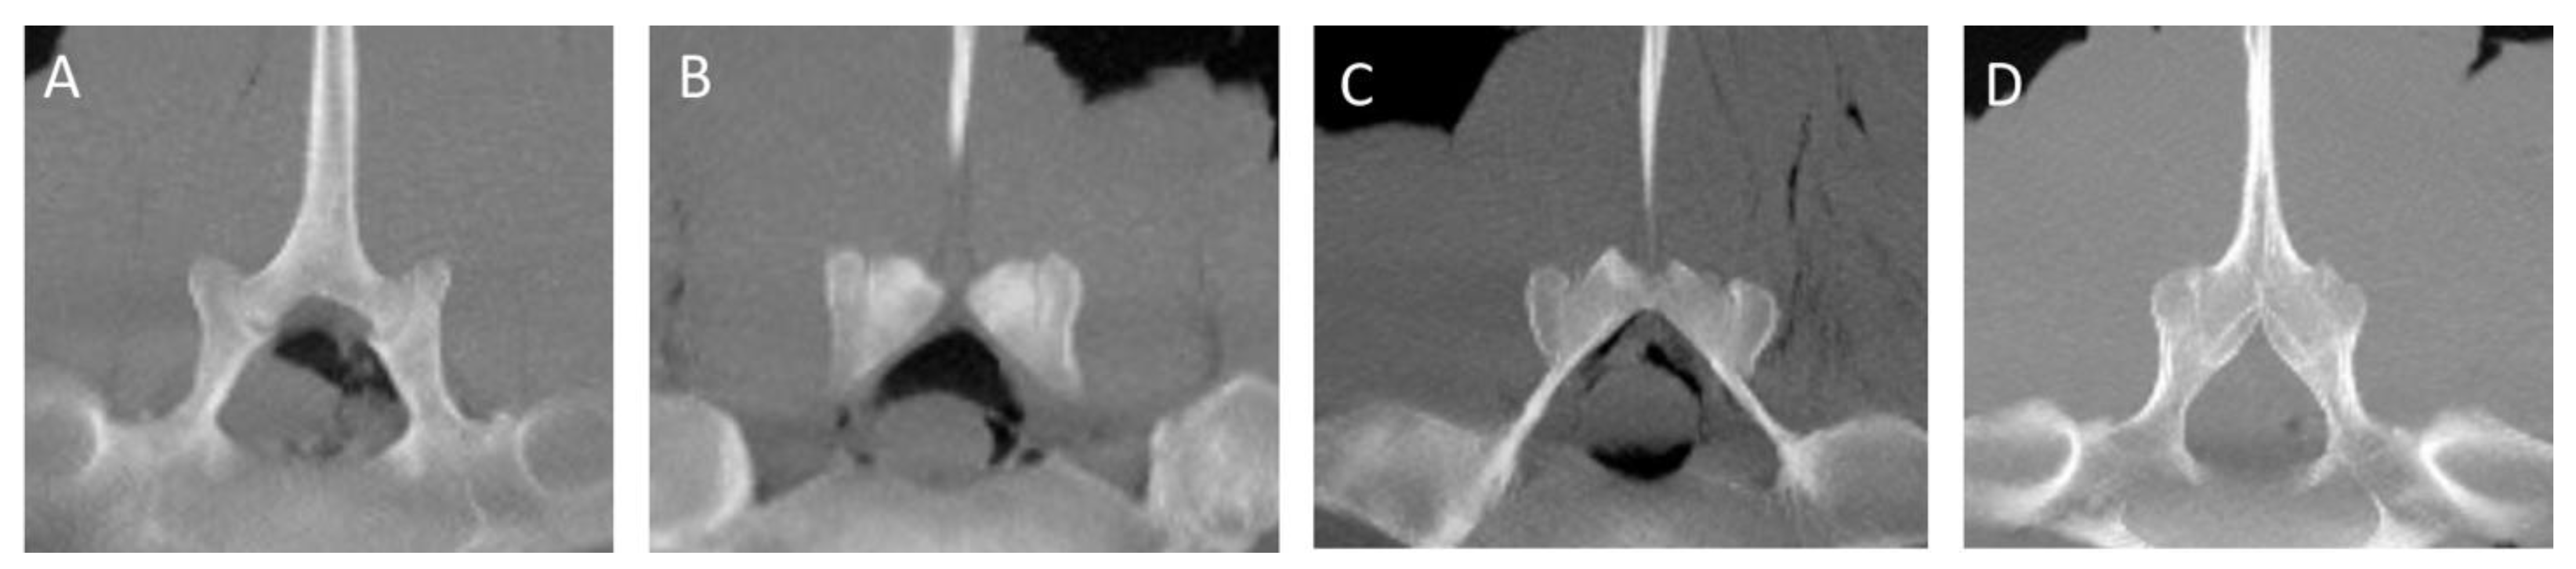

There was a correlation between both the left and right lengths (r = 0.6) of the L(ii)-L(i) ITJs and mean bone density (HU) of the adjacent bone on the left and right sides (r = 0.7) (both p < 0.001). The detected bony changes and their symmetry in the APJs from L(iv)-L(iii) to L(ii)-L(i) (Figure 5) are summarized in Table 4.

Figure 5. Transverse multiplanar reconstruction computed tomographic images (AD) of the lumbar specimens 12, 23, 34, and 25, using maximum intensity projection (MIP); the dorsal is toward the top of the images. There are bilateral mild (A), moderate (B), and severe (C) periarticular osseous changes involving the cranial aspect of the L(ii)-L(i) articular processes joints (APJs). (D) There is also complete obliteration of the APJs joint space (ankylosis). L(ii): second to the most caudal lumbar vertebra; L(i): the most caudal lumbar vertebra.